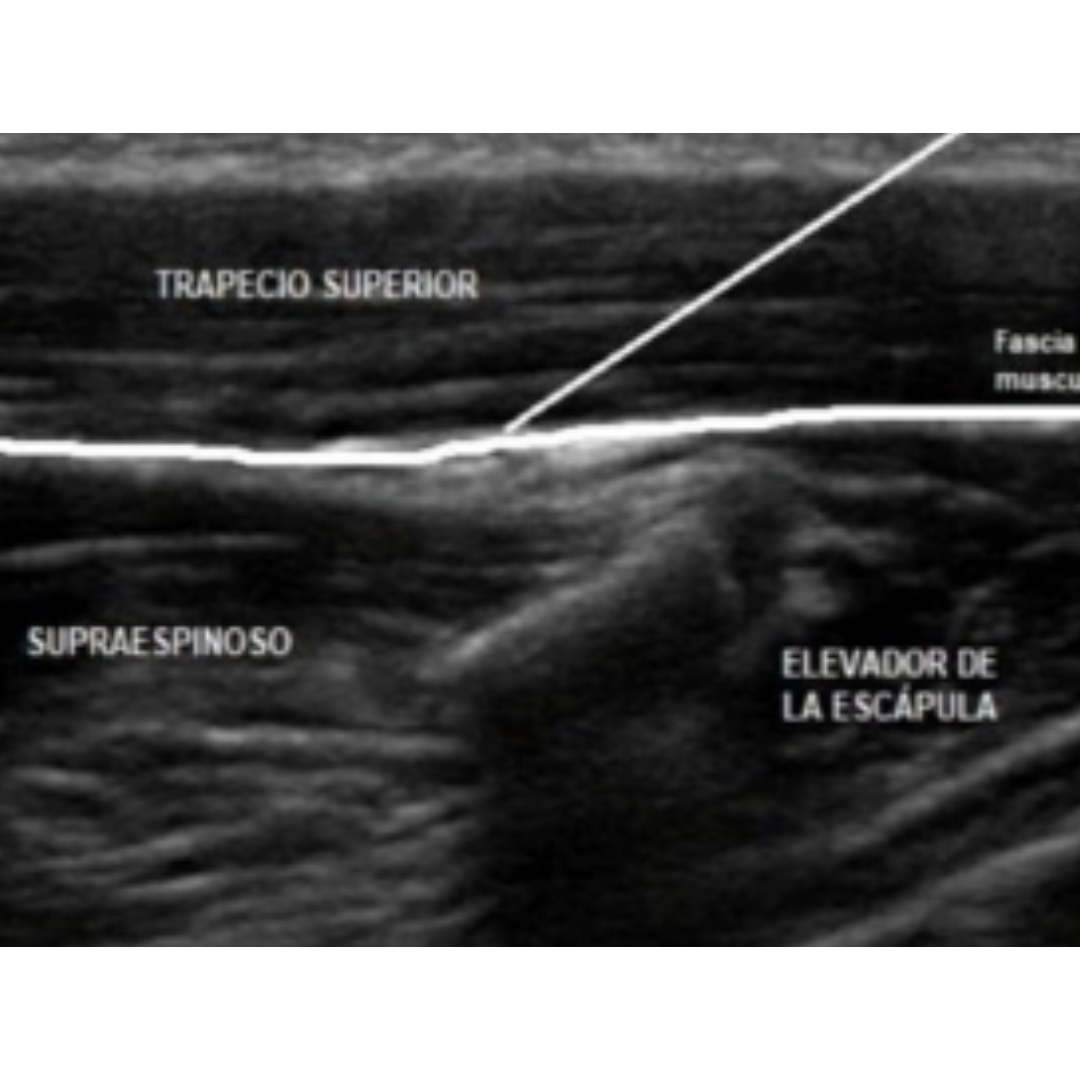

Imagen 3: Desde superficial a profundo: piel-subcutáneo-trapecio-supraespinoso-escápula.